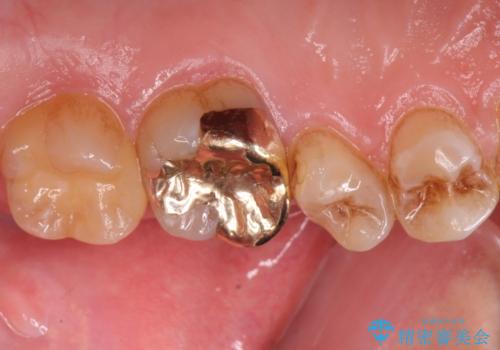

1本はゴールドアンレー、もう1本はセラミックインレーで修復します。

- 左上6/ゴールドアンレー:110,000円 左上7/セラミックインレー:77,000円費用は治療当時の料金となります

患者様の咬む力や削るべき歯の量によって、使用する材料を決めております。